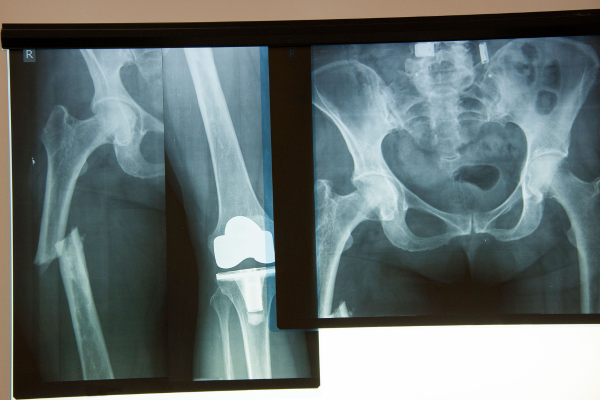

Our Hip Procedures

Hip Arthroscopy

img

Hip Cartilage Repair

Read More

Hip Fracture Surgery

Hip Labral Repair

Total Hip Replacement